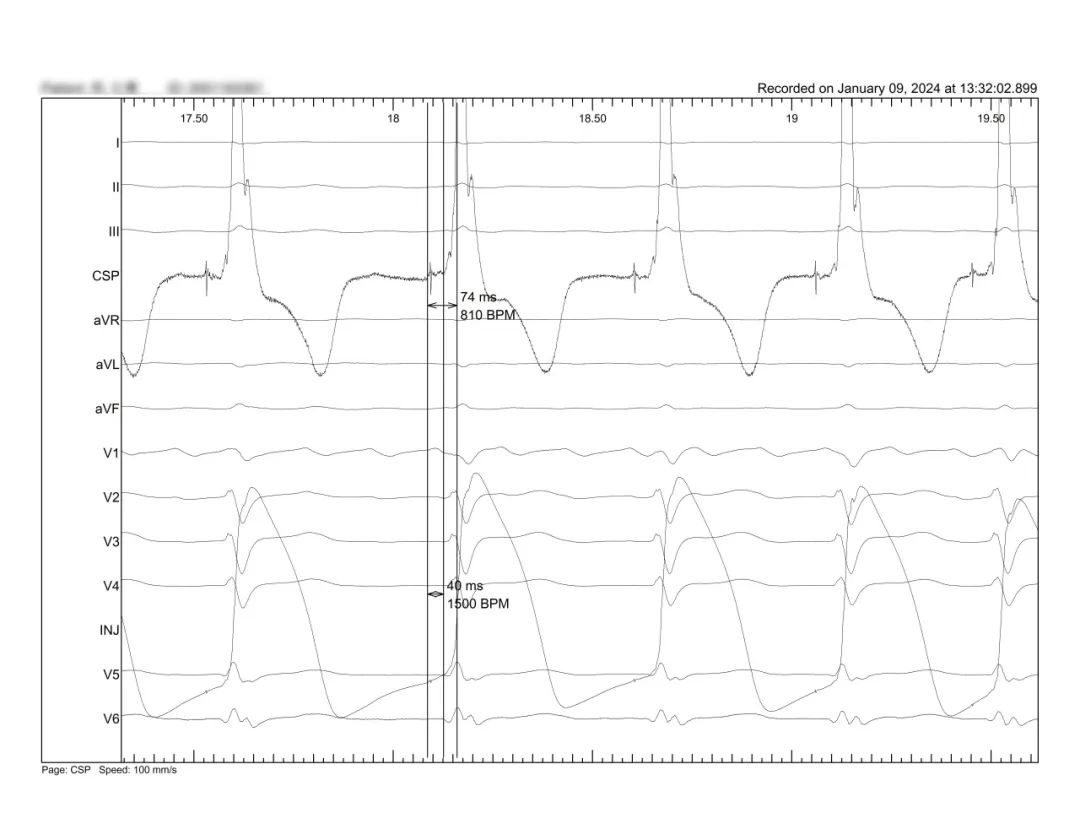

术后融合:DDD SAV:120,单LV双极起搏 2.5V输出

温州医科大学附属第一医院CSAE

AF快心室率心衰房室结消融电位损伤消融靶点

另外,在手术演示间隙的MINI TALK环节中,复旦大学附属中山医院陈学颖教授讨论了损伤电流在左束支起搏术中的应用价值。同时,江苏省人民医院侯小锋教授对左束支起搏术中的起搏测试进行了精彩的演讲。此外,温州医科大学附属第一医院苏蓝教授则对如何选择右室面拧入点做了详细说明。这些讨论和演讲内容丰富,对手术操作具有重要指导意义。